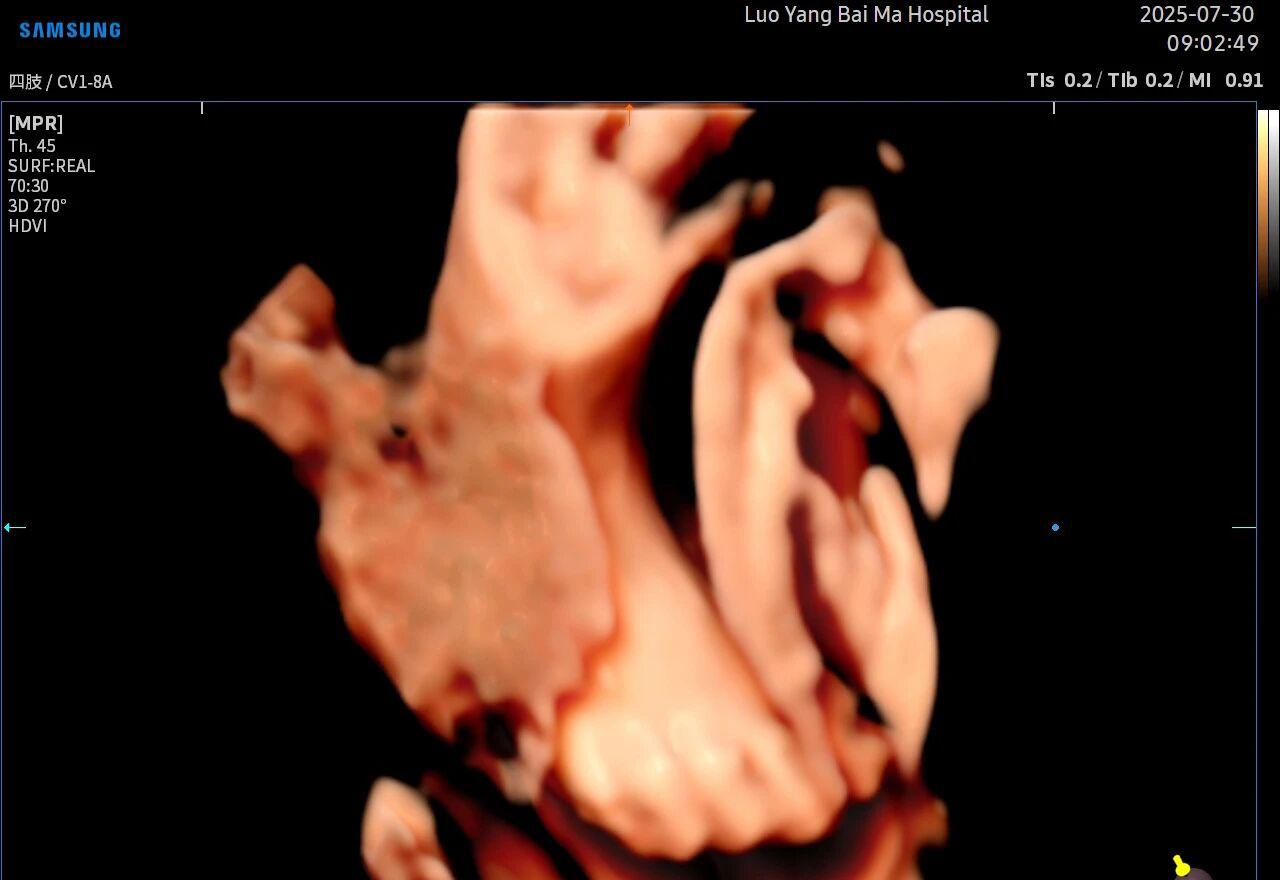

5D智能彩超拥有更高的分辨率和更强的图像处理能力,能够呈现出接近“IMAX电影画质”的细腻影像 。它采用一种被称为“水晶成像”的技术,能够穿透组织,将胎儿的骨骼、器官和组织结构以极其清晰、立体的形态展示出来。这种高清晰度对于观察胎儿微小的解剖结构细节至关重要,例如手指、脚趾、耳廓形态等,有助于医生发现一些在传统超声下不易察觉的细微异常,为排畸诊断提供了更丰富的视觉信息。

传统超声检查有时会因为胎儿体位、羊水量等因素的限制,导致某些部位观察不清。5D智能彩超技术能够实现对目标结构进行360°全方位、多切面的自由旋转观察。医生可以像“雕塑家”一样,从任意角度审视胎儿的解剖结构,尤其对于形态复杂的心脏、颅脑和脊柱等部位,这种能力可以极大弥补单一平面的局限性,帮助医生更全面地评估其发育状况。